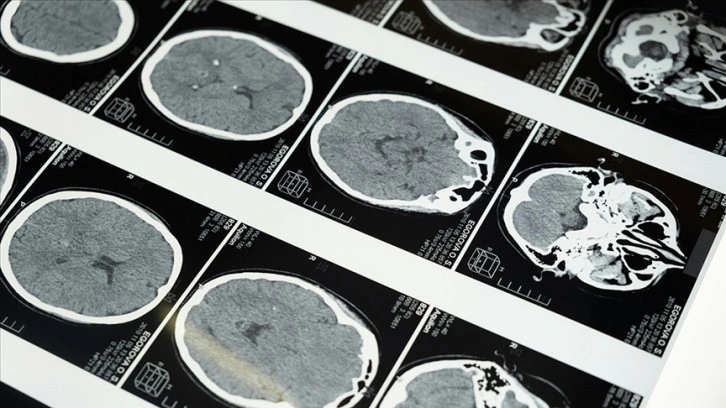

Yapılan çalışmalar kapsamında MRI cihazının son birkaç ay içerisinde yaklaşık 20 sağlıklı gönüllü üzerinde test edildiği kaydedilen açıklamada, neredeyse 4 dakikada en net beyin görüntüsünün elde edildiği aktarıldı.

Açıklamada, 11,7 Tesla manyetik güce sahip Iseult MRI makinesiyle kısa sürede çekilen görüntülerin, hastanelerde yaygın kullanılan cihazlarla elde edilmesinin saatler sürebileceği kaydedildi.

Iseult MRI cihazı ile elde edilen ultra detaylı anatomik bilgilerin, Alzaymır ve Parkinson gibi hastalıkların teşhisinde yardımcı olması bekleniyor.